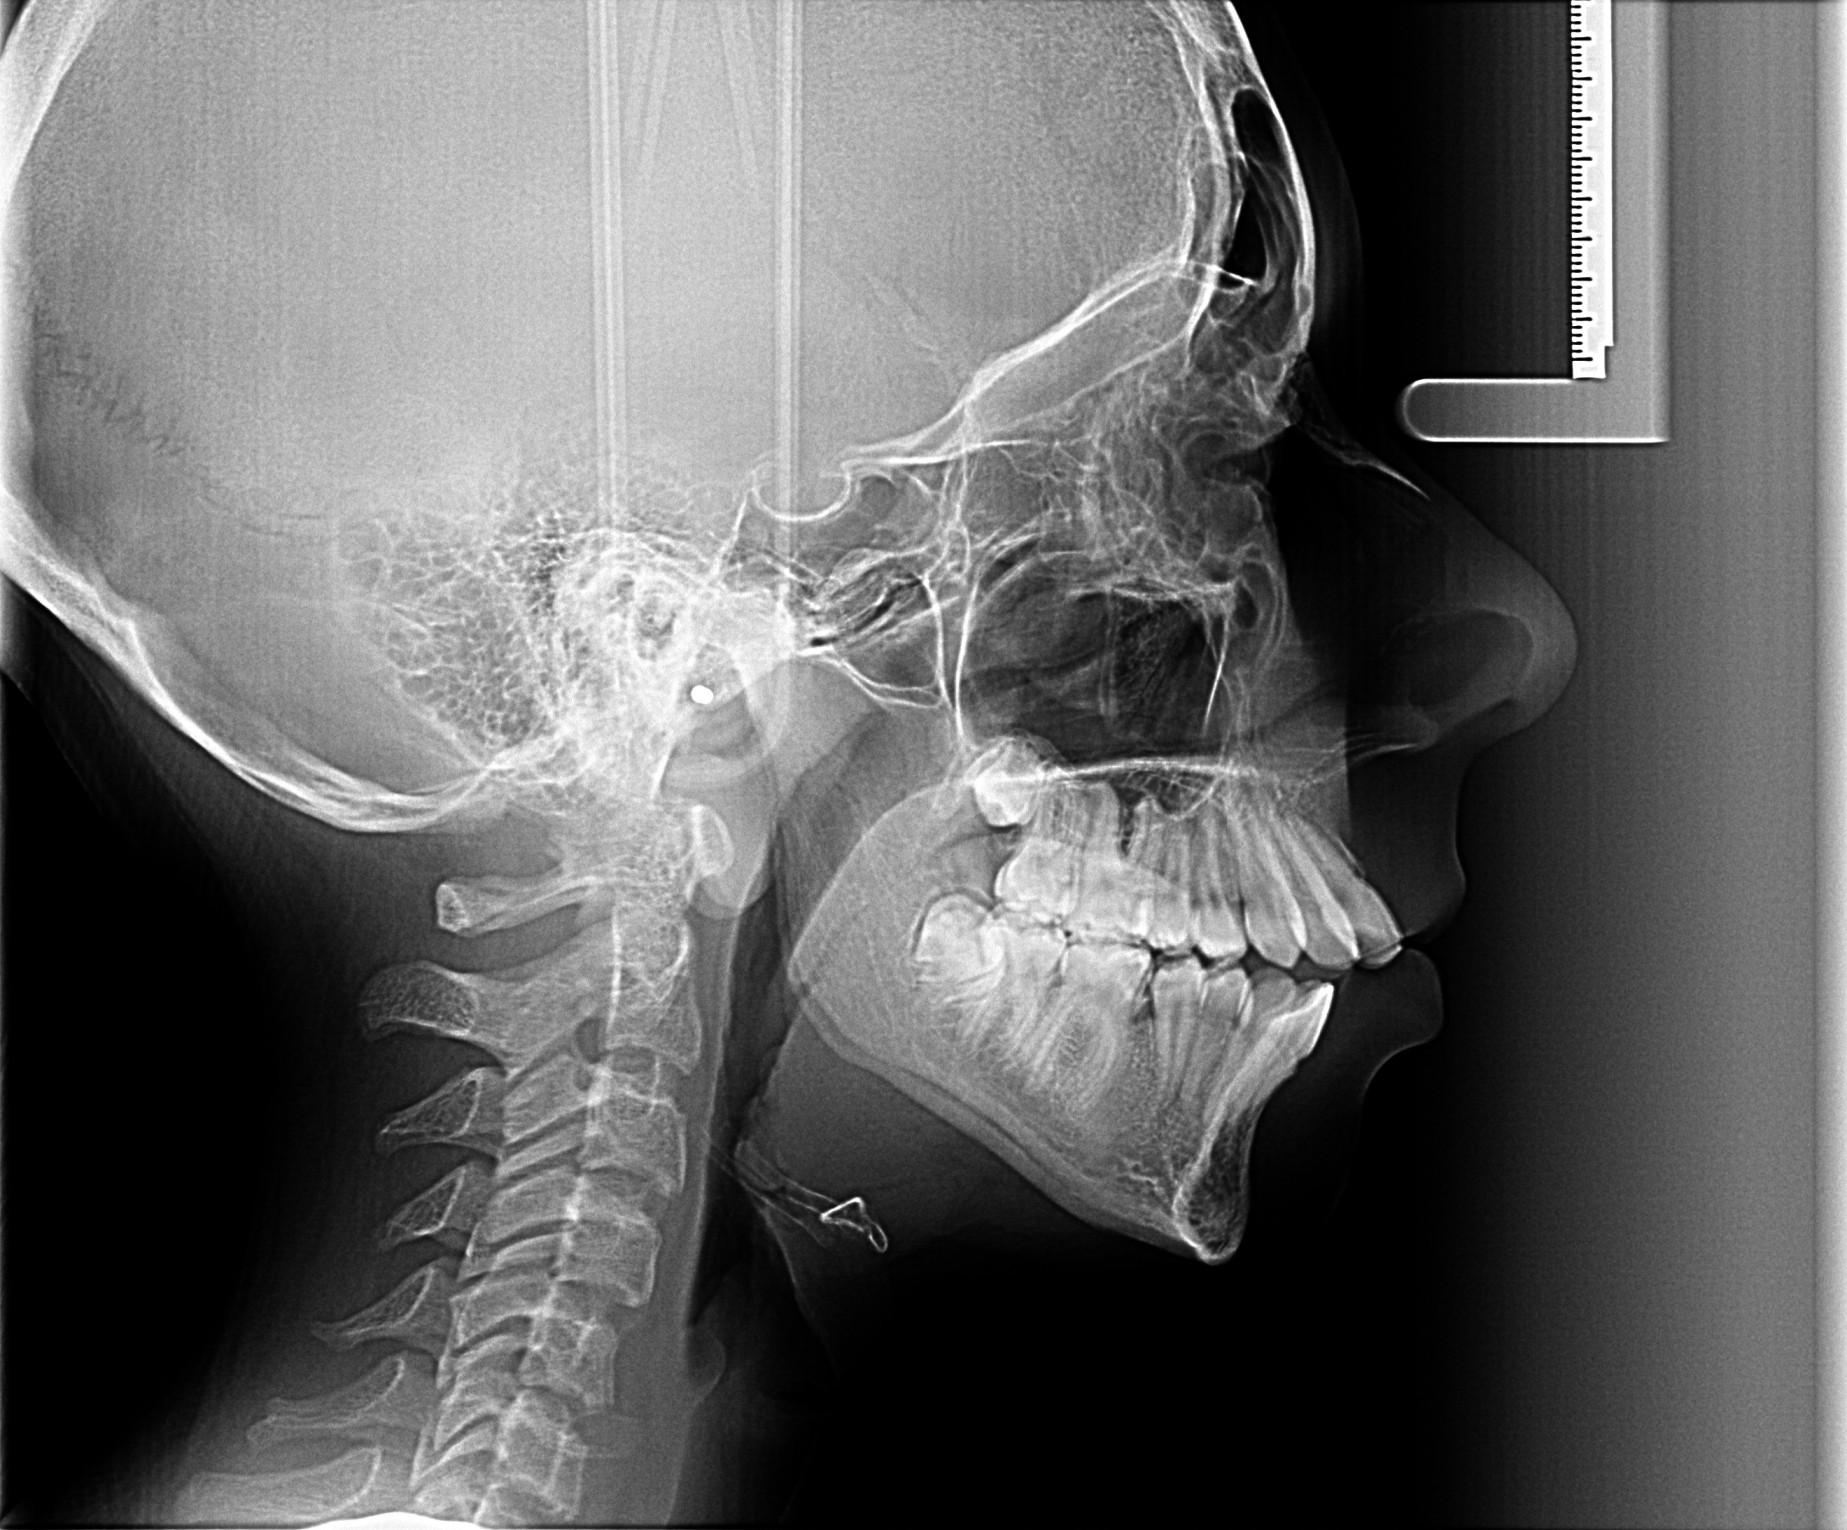

Descriere

Oferă o imagine de ansamblu a oaselor viscerocraniene și parțial a celor craniene, ajutând la stabilirea diagnosticului în ortodonție și chirurgia maxilo-facială.

Imaginea evidențiază și evoluția osificării vertebrelor cervicale, ceea ce permite medicului specialist stabilirea evoluției pre- și post-pubertare a pacientului.